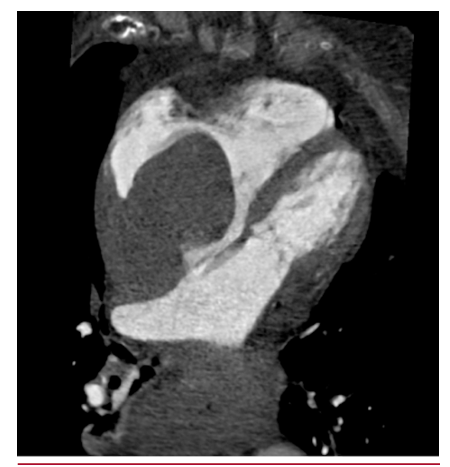

Linfoma cardíaco primario